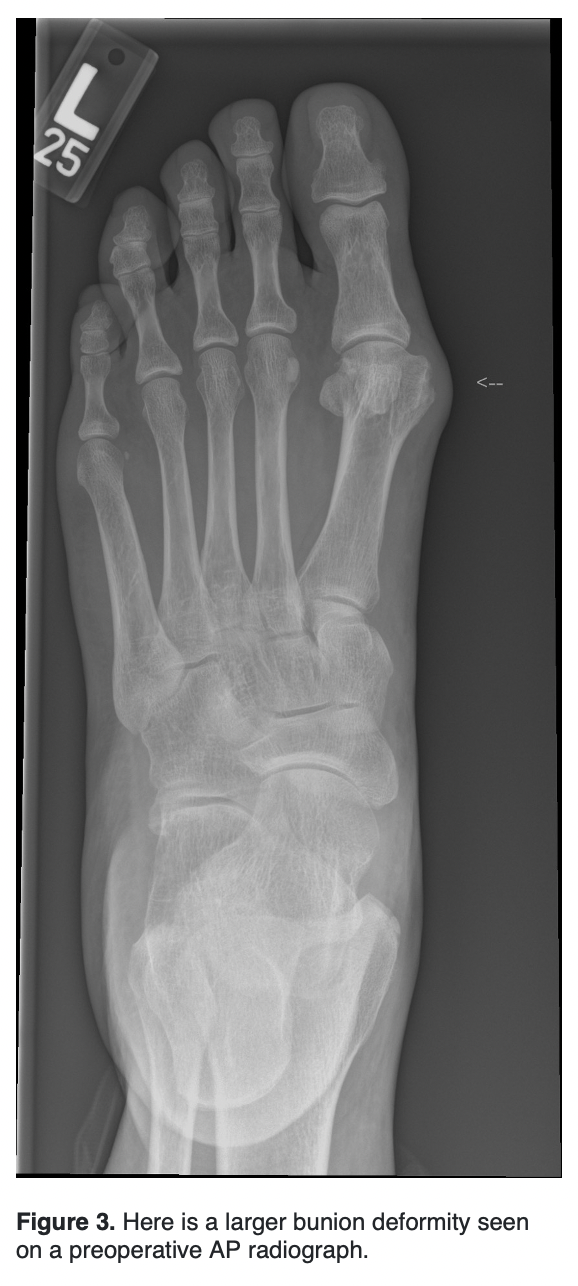

With advancing technology, new emerging bunion techniques have evolved, the newest concept being innovations in minimally invasive surgery (MIS). The question, however, is, “What procedure should surgeons do for a larger bunion deformity?”

Traditionally, surgeons used the Lapidus and proximal osteotomies of the first metatarsal to correct larger bunion deformities. In the last several years, it has become increasingly common to correct larger bunion deformities with distal MIS osteotomies. Here, the authors review the current literature on correcting larger bunion deformities with both Lapidus and MIS techniques.

Severe hallux valgus is categorized as an intermetatarsal (IM) angle of greater than or equal to 20 degrees and a hallux valgus angle (HAV) of greater than 40 degrees.